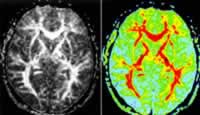

顱內脊索瘤X線表現頭顱脊索瘤多見於顱底、蝶鞍附近,蝶枕軟骨連合處及岩骨等處。骨質破壞邊界尚清楚,可有碎骨小片殘留和斑片狀鈣化物質沉積。並可有軟組織腫塊凸入鼻咽腔,一般較大,邊緣光滑。脊索瘤腫塊突出顱腔時可使鈣化松果體移位,偶可引起顱內高壓。頸椎的脊索瘤常位於上頸椎,尤在頸椎和枕骨交界處,多累及椎體、椎弓根偶爾也可受到侵犯,軟組織腫塊,常為突出的早期表現。胸椎脊索瘤較少見。